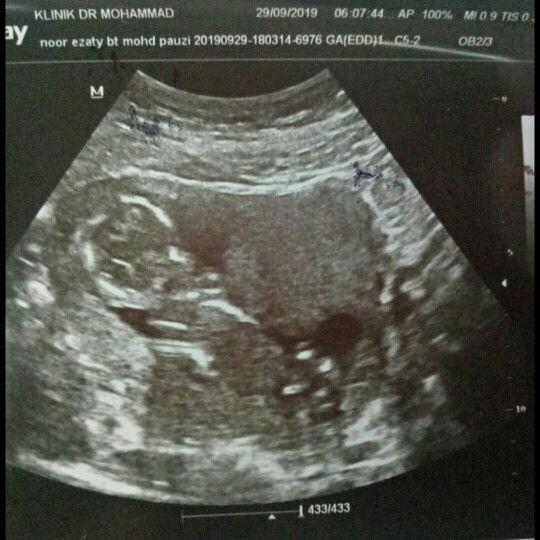

rahim ada air

semalam saja2 pegi scan, then doc bgtau perkembangan janin semua, tiba2 doc tnya ada keluar mcm air tak? saya tnya kenapa doc? doc terangkan yang rahim saya mcm byk air, sapa penah ada pengalaman mcm saya? bahaya tak kepada janin?